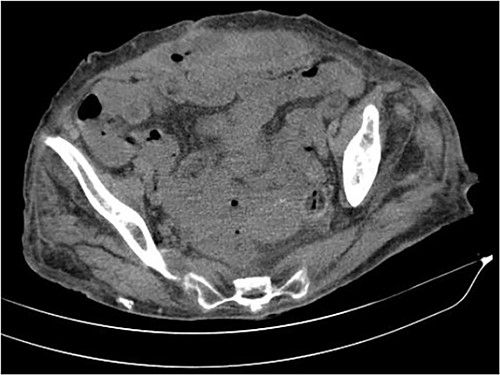

The abdominal computed tomography (CT) scan showed an abscess in the abdominal wall adjacent to the previous mesh, measured 12 × 4.0 × 13.0 cm (Fig. 2). The patient’s laboratory test results showed a mild elevation of protein C-reactive (70.9 mg/L) with normal levels of white blood cells. The patient’s renal function and electrolyte levels were within normal limits.

The axial CT section of the abdomen showing an abscess in the abdominal wall adjacent measured 12 × 4.0 × 13.0 cm.